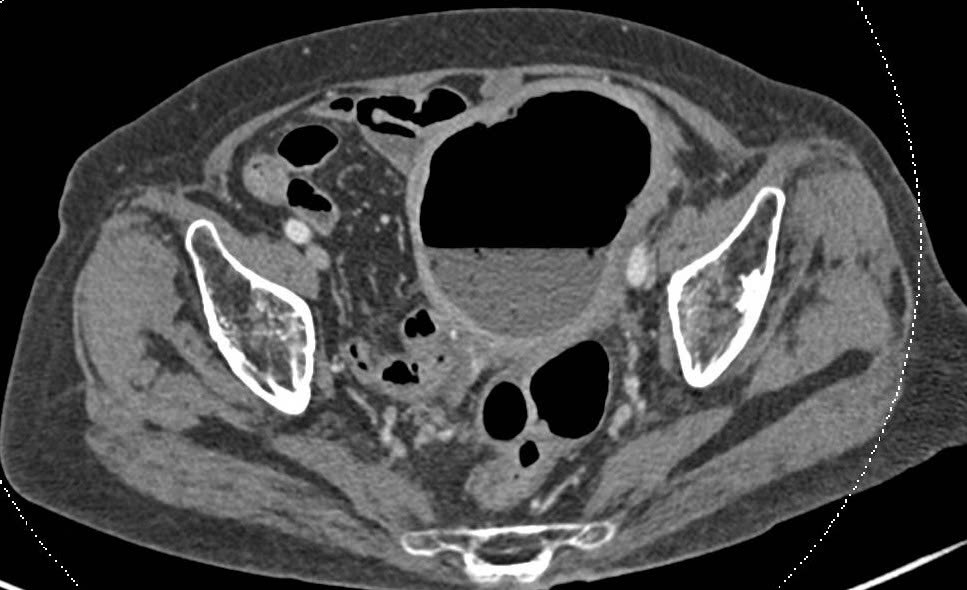

Cụ M.T.M. (88 tuổi, TPHCM) được người nhà đưa đến Bệnh viện FV trong tình trạng sốt, đau bụng âm ỉ không dứt, âm đạo tiết dịch mủ. ThS.BS Lê Đức Tuấn - Khoa Ngoại tổng quát chỉ định chụp CT ổ bụng. Hình ảnh cho thấy tử cung to bất thường, chứa đầy dịch và khí. Cụ được chỉ định nội soi đại tràng và lòng tử cung, kết quả khẳng định: phân xuất hiện trong khoang tử cung - dấu hiệu của rò âm đạo trực tràng, nếu không được xử lý kịp thời sẽ nguy hiểm tới tính mạng.

Phim chụp CT cho thấy tử cung có kích thước lớn bất thường, chứa nhiều khí và dịch. Ảnh: FV